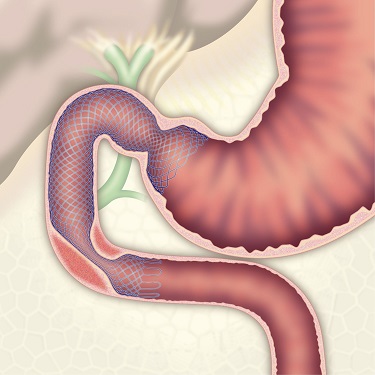

コールドスネアポリペクトミー(CSP)

合併症の非常に少ない優れた治療法であることから、近年大腸ポリープの外来切除法として急速に施行件数が増えてきています。当院ではこのコールドスネアポリペクトミーを主体としたポリープ切除を行っています。

| 3:病変をスネアに通します。 | 4:周囲の正常粘膜をしっかり入れながら、病変を絞扼していき... | |